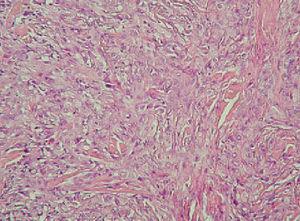

Fig. 1.Imagen anatomopatológica. (Hematoxilina-eosina, ×100.)

La histopatología mostraba piel con la dermis e hipodermis infiltradas por una neoplasia no encapsulada, de bordes estrellados e infiltrantes, constituida por células fusiformes y epitelioides, de núcleos con atipias citológicas, pequeño nucléolo ocasional, y citoplasma eosinófilo amplio o claro, de límites netos. Se disponían formando nidos, cordones o nódulos, in-completamente delimitados y separados por tabiques fibroconjuntivos, con necrosis central y células epitelioides rodeándolos, que le conferían un aspecto granulomatoso, con una extensión de aproximadamente el 5 % de toda la neoplasia. Las células neoplásicas presentaban una marcada actividad mitótica, con presencia de mitosis típicas o atípicas, con un índice mitótico de 5 mitosis por 10 campos de gran aumento.

Histológicamente está definido por una proliferación de células fusiformes, poliédricas, epitelioides, de citoplasma muy eosinófilo y núcleo grande. Estas células se disponen formando nódulos bien definidos no encapsulados en la dermis y la hipodermis, centrados por zonas de necrosis. Es por esta disposición, que recuerda a los granulomas, que desde el punto de vista anatomopatológico puede confundirse con múltiples enfermedades de naturaleza benigna inflamatoria o infecciosa como los granulomas anular, sarcoideo o tuberculoso, la necrobiosis lipoídica, el nódulo reumatoideo, la fascitis nodular o la tenosinovitis. También puede confundirse con procesos tumorales como carcinomas escamosos y anexiales, melanoma y tumores malignos vasculares epitelioides. Algunos sar-comas epitelioides presentan células rabdoides grandes de gran atipia citológica, con citoplasma eosinófilo y núcleo excéntrico, por lo que debe el diagnóstico diferencial plantearse con el tumor maligno rabdoide extrarrenal. Presenta dificultad diagnóstica al asemejarse a otros sarcomas de aspecto pseudoepitelial como schwannoma maligno epitelial, hemangioendotelioma epitelioide y, sobre todo, con el sarcoma sino-vial, más aún si profundiza en dermis e hipodermis y se adhiere a fascia o tendón.